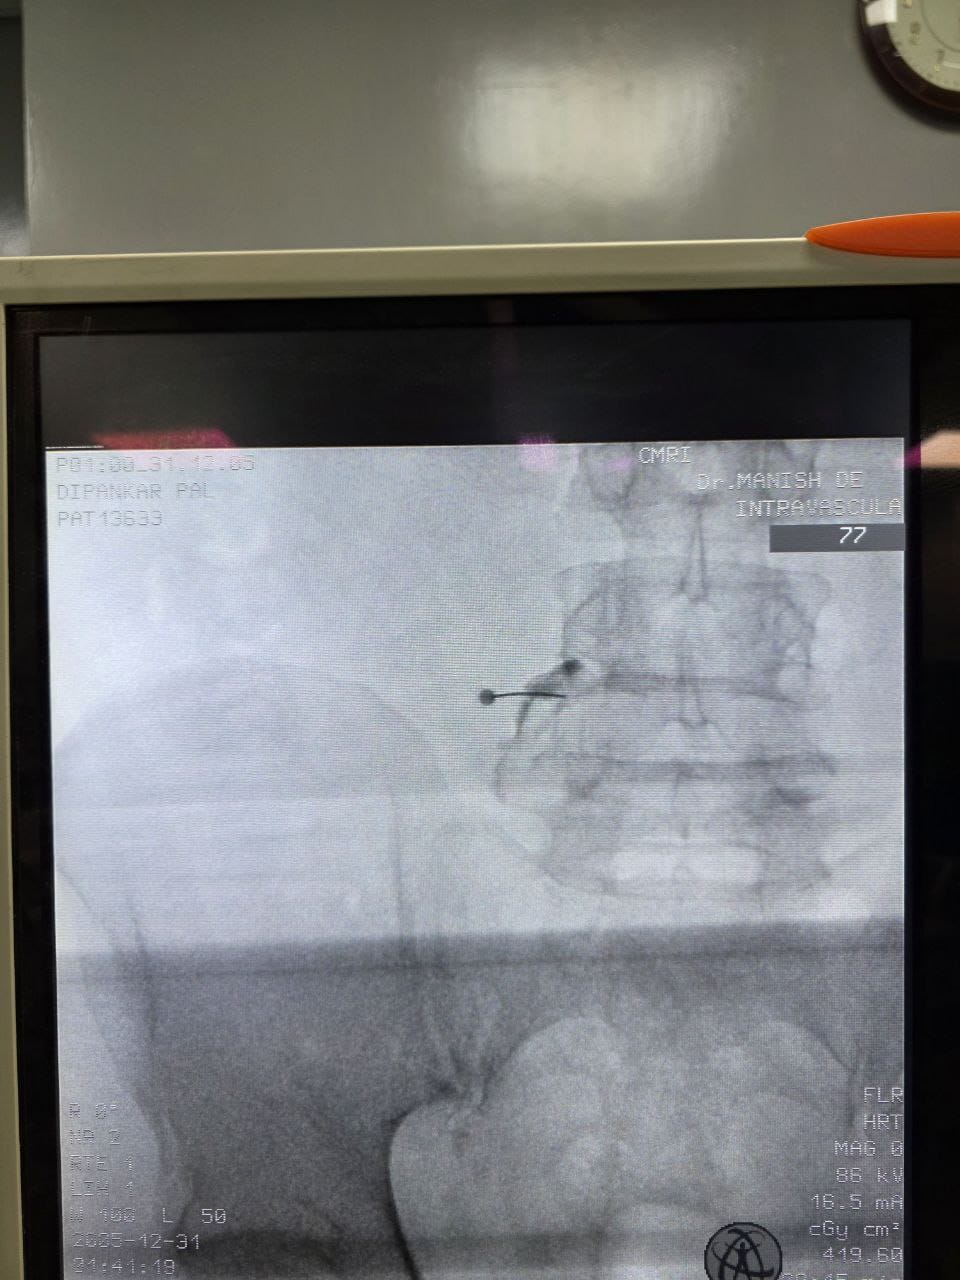

Procedures

Struggling with chronic pain? Get advanced, personalised pain management from Dr. Manish De, one of Kolkata’s leading pain specialists. From knee pain, heel pain, low back pain, frozen shoulder, migraines, cancer pain to post-TKR persistent pain—Dr. De offers safe, evidence-based treatments across multiple locations: